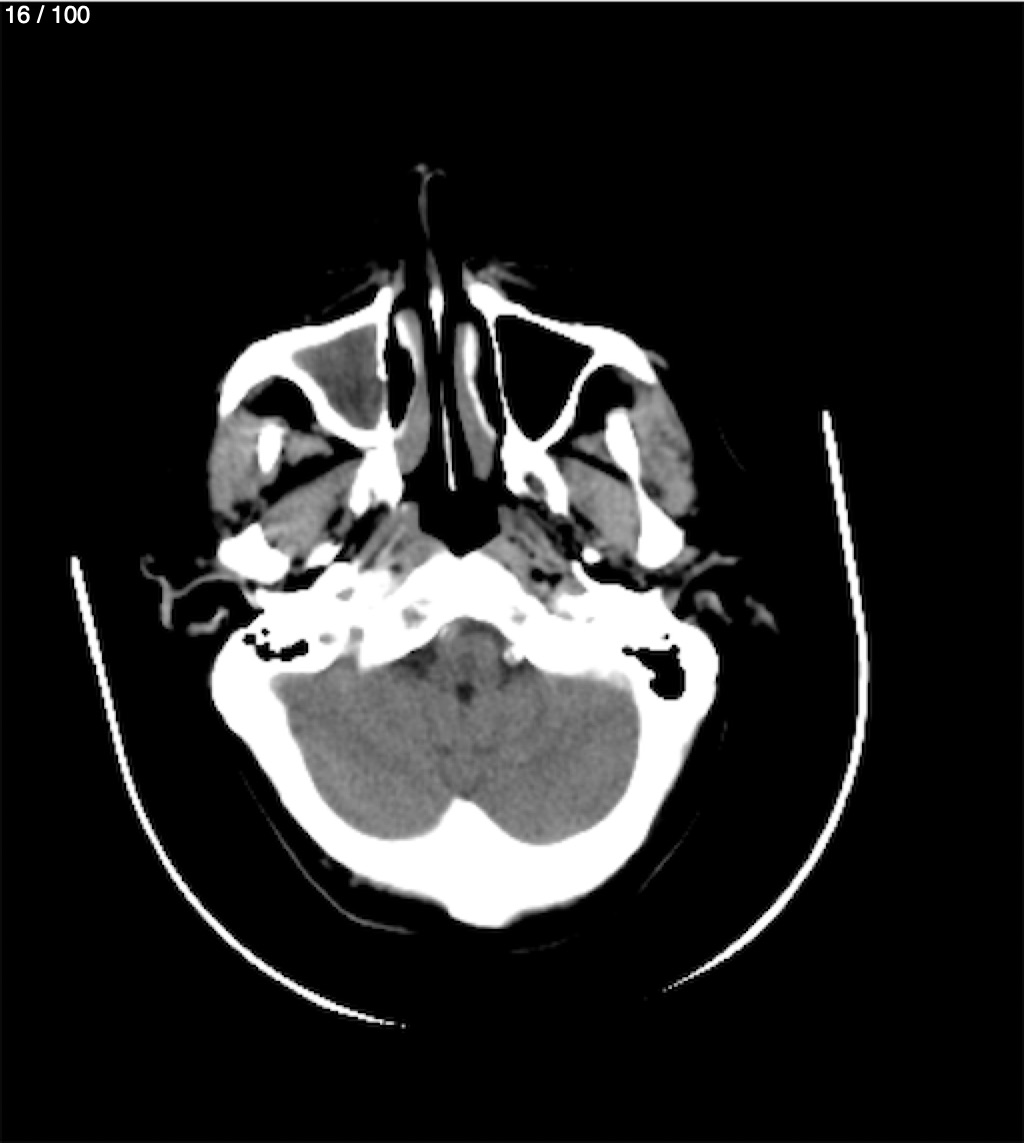

Valentin Perez Gomez 69A - T.C Craneo